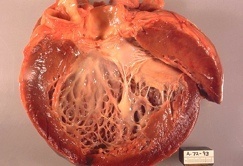

Anatomía patológica

Alteraciones macroscópicas:

• El corazón suele estar agrandado, pesa más y tiene una consistencia blanda, debido a la dilatación de todas las cavidades.

• Los trombos parietales son frecuentes y son una fuente posible de émbolos.

• No existen alteraciones valvulares primarias, y cuando hay insuficiencia mitral (o tricuspídea), se relaciona con la dilatación sufrida por la cavidad ventricular.

Alteraciones histológicas:

• Son inespecíficas y no suelen señalar hacia ningún agente causal concreto.